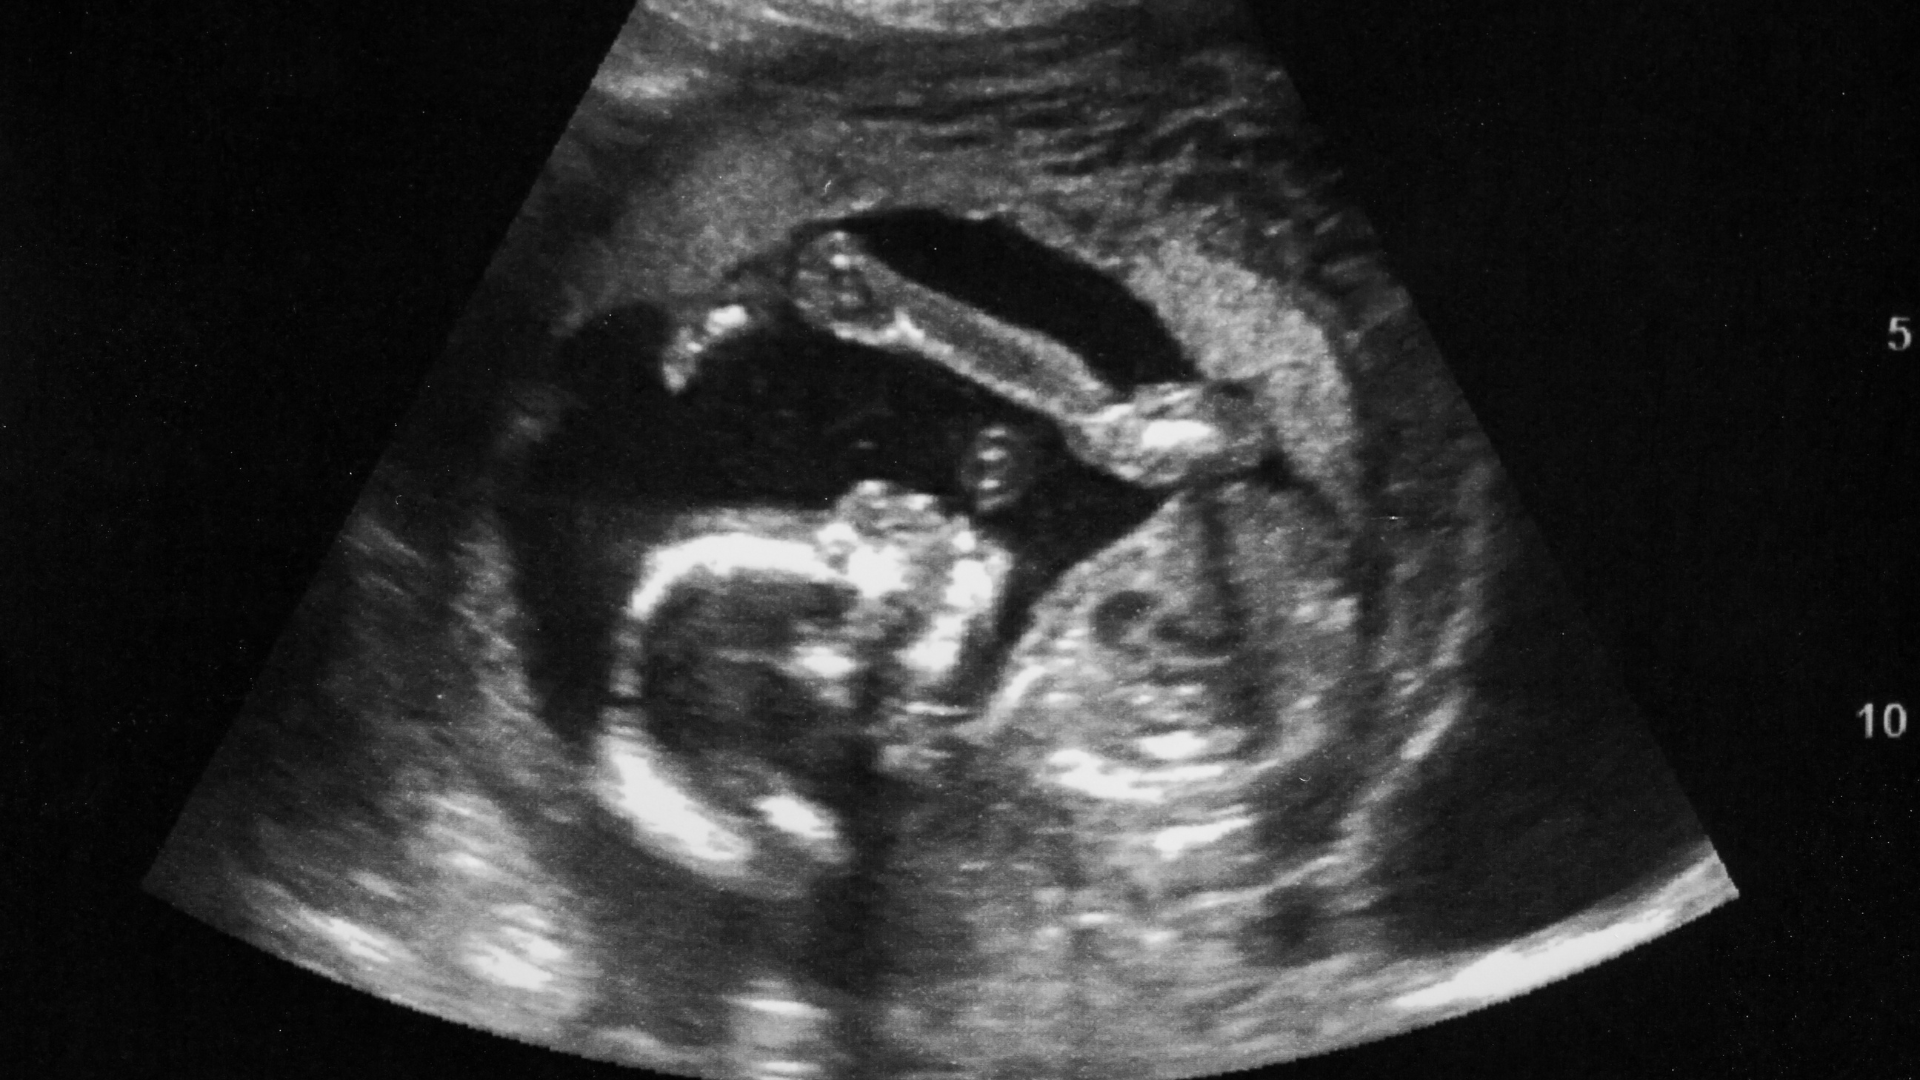

Đa ối thường được phát hiện qua siêu âm và đo chỉ số AFI.

Khám thai định kỳ để theo dõi lượng nước ối

Siêu âm định kỳ giúp bác sĩ đo chỉ số AFI hoặc DVP để đánh giá lượng nước ối. Việc tuân thủ lịch khám thai là yếu tố quan trọng nhất giúp phát hiện sớm đa ối, thiểu ối hoặc nước ối đục, từ đó có hướng xử trí phù hợp ngay từ đầu.